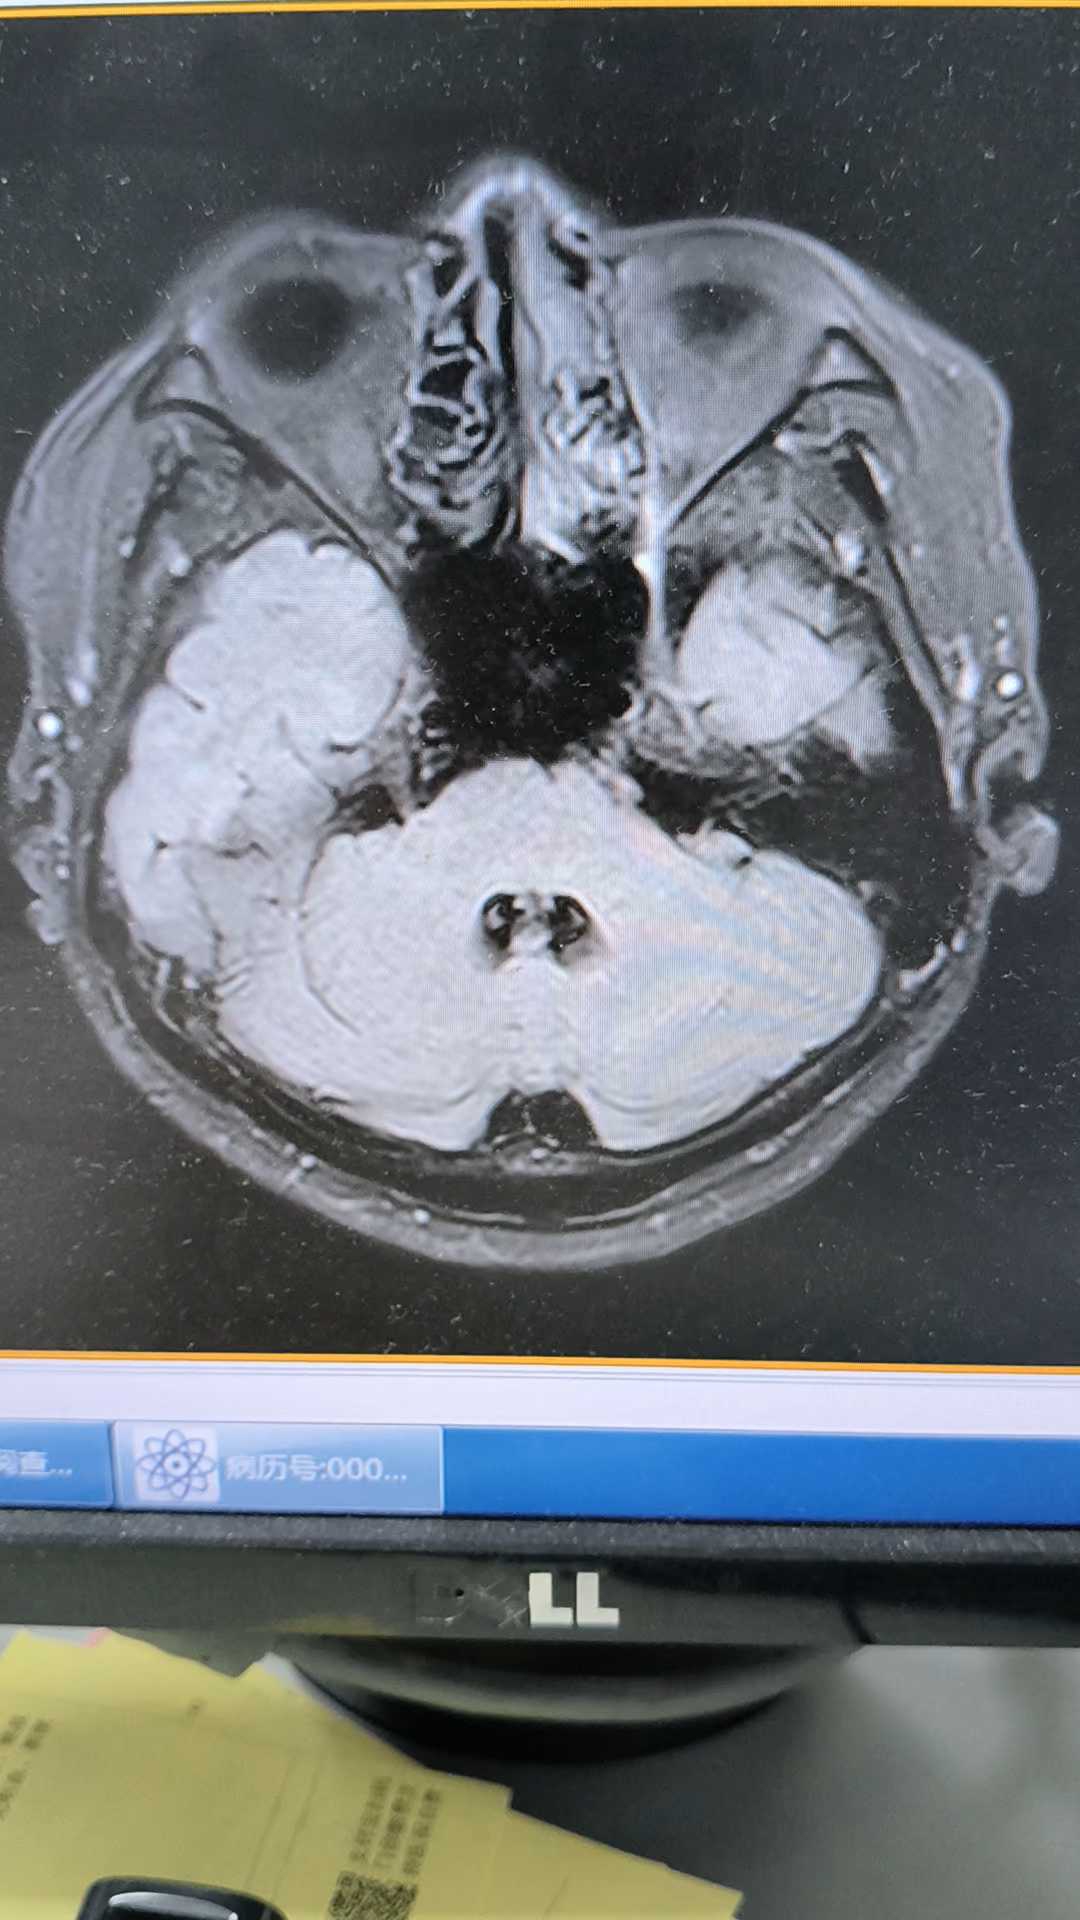

病例中年男性39岁,四肢抽搐入院

磁共振提示什么?